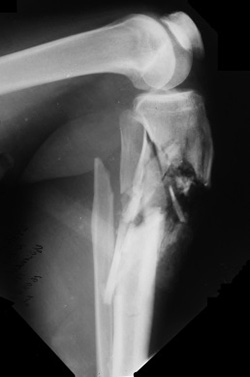

Классификация открытых переломов:

Классификация открытых переломов по Gustilo-Anderson.

Тип III

1. Диафизарный перелом с расхождением и потерей сегмента;

2. Перелом с повреждением магистральных сосудов;

3. Сильно загрязненные раны, или раны с заражением;

4. Травмы, полученные при столкновении транспортных средств на большой скорости;

5. Рана от вохдействия высокой энергии;

6. Сегментарный тип переломов.

Тип III А

1. Рана более 10 см с размозженными мягкими тканями;

2. Сильное загрязнение;

3. Кость, как правило, прикрыта мягкими тканями.

Тип III B

3. Мягкие ткани не прикрывают кость, требуется их пластическое восстановление.

Тип III C

1. Переломы с массивным повреждением сосудов;

2. Требуют сосудистого шва для сохранения конечности.